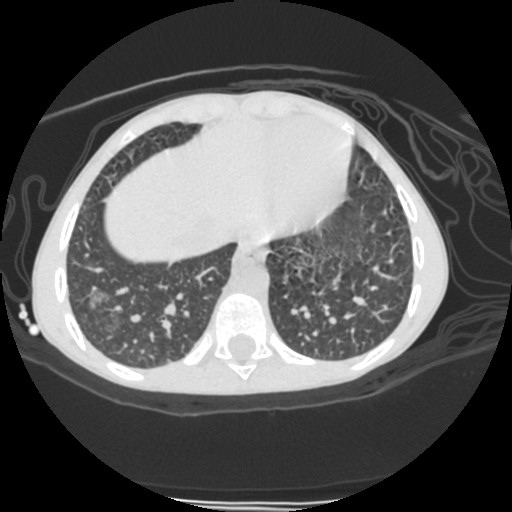

- Computerized tomography (CT) of chest.

| CT3 | CT4 | CT5 |

| CT1 | CT2 |